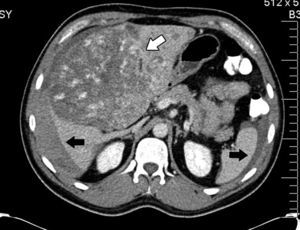

His condition began in March 2012 with sharp abdominal pain in the epigastrium which later spread to the whole abdomen. He presented with haemodynamic instability and therefore presented at the hospital in Houston, Texas, U.S.A. (his place of residence at the time), where massive intrabdominal bleeding was diagnosed secondary to cavernous haemangioma, bilobular in appearance (Fig. 1); angiographic embolisation was performed, with cessation of bleeding. When the patient had recovered an orthotopic liver transplant of the right lobe was performed, with blood type compatibility, with standard surgical reconstruction for the live donor in May 2012, in a private hospital in the city of after Guadalajara, Jalisco. Positive serology for CMV IgG for both the donor and the recipient was present. The patient was discharged 8 days after surgical procedure with immunosuppression therapy which included tacrolimus, mycophenolic acid and prednisone.

Abdominal axial CT scan with oral and intravenous contrast enhancement in arterial phase which shows liquid fluid in the abdominal cavity, predominantly perihepatic and perissplenic (black arrows) and a rounded tumour, heterogeneously contrasted, which occupies practically the entire liver (white arrow).